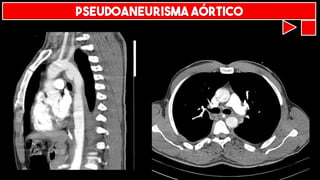

PSEUDOANEURISMA AÓRTICO

LACERAÇÃO AÓRTICA

TRANSECÇÃO AÓRTICA